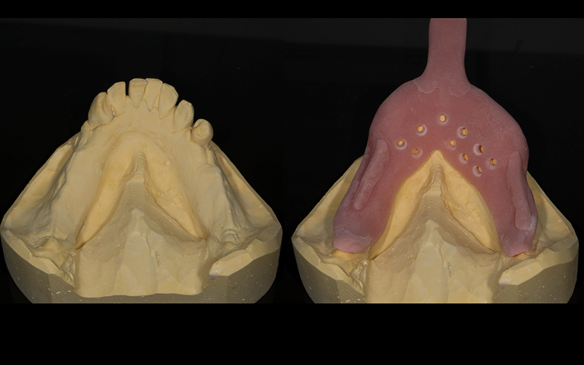

This newsletter describes in step by step detail the transition from acrylic based immediate dentures to metal based definitive dentures.

- Extraction of all upper teeth and LR5 and LL4 and fitting of immediate acrylic based (Mk 1) dentures - complete upper and lower partial

- Definitive dentures (Mk 2) – complete upper metal reinforced and lower cobalt chromium based partial of hygienic Scandinavian design to be made 9 - 12 months after extractions of all upper teeth and LR5 and LL4